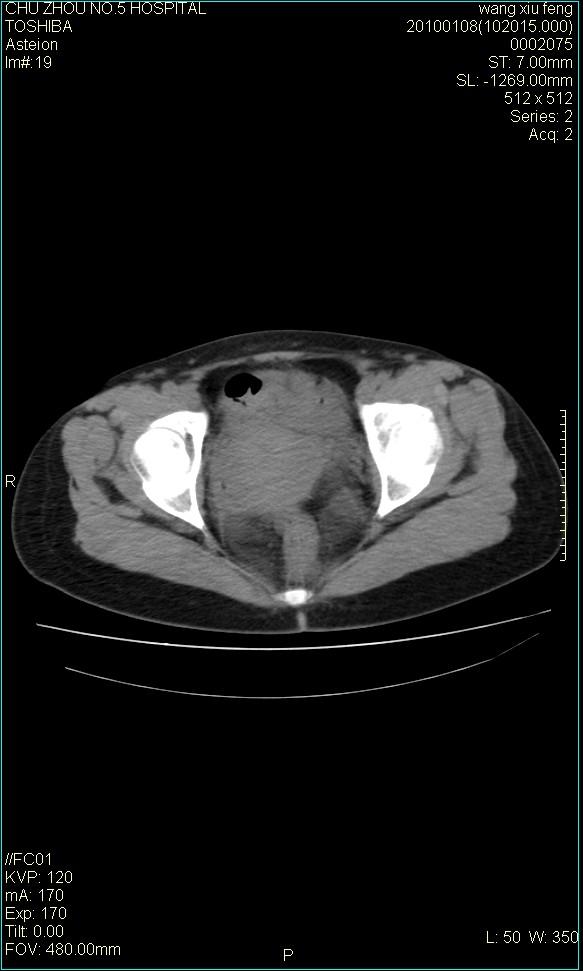

f-41,左乳腺ca术后4年,b超示:子宫右上方囊性包块约5.5*3.4cm,前日行胸部ct平扫未见明显异常。

考虑右侧卵巢囊腺瘤?

右侧卵巢囊肿或小囊腺瘤。

考虑右侧卵巢囊腺瘤?建议增强!

考虑右侧卵巢囊腺瘤。

考虑右侧卵巢囊性占位性病变(囊肿?囊腺瘤?)。